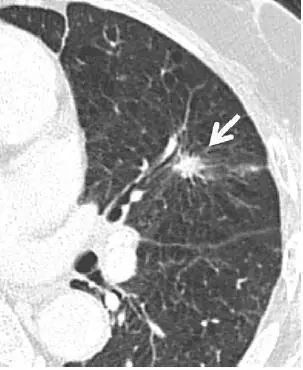

5. 肺内淋巴结

图 5 CT 图像,显示一个三角形实性胸膜下结节(箭头),且呈线状延伸至胸膜表面,为典型的肺内淋巴结表现,不建议 CT 随访。